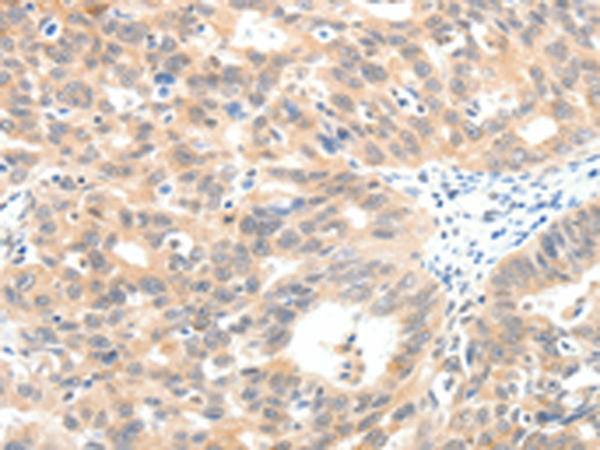

IHC positive control: |

Human ovarian cancer |

IHC Recommend dilution: |

25-100 |